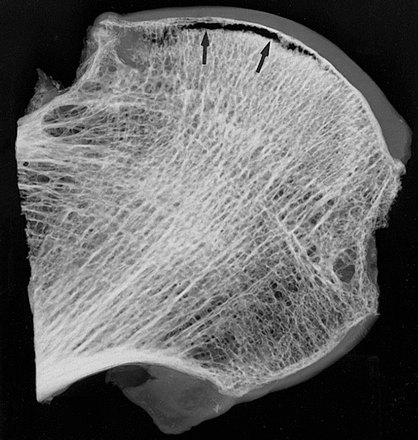

Arrows show the trabecular subchondral fracture plane, low in signal (black) on mri (a). Clinically, sif has generally been observed in the osteoporotic elderly women or renal transplant recipients. A subchondral fracture was seen in 12 out of 32 infarcted femoral heads (38%) that were in the initial radiographic stage of ischemic osteonecrosis.

These are often seen in the tibial plateaus, tibial condyles, femoral condyles or the patella.